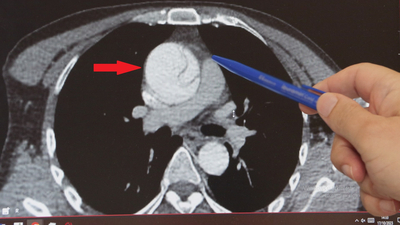

Daha önce hiçbir sağlık sorunu olmayan 41 yaşındaki Mustafa Turan, birkaç hafta önce arkadaşlarıyla ayak üstü sohbet ederken "Göğsümde yırtılırcasına bir ağrı başladı" diyerek fenalaştı ve acile kaldırıldı. Kalp ekosu çekildi, çeşitli tahliller yapıldı ancak her şey normal görünüyordu. Ağrılarının midesinden olabileceği düşünüldü ve gerekli tedavileri verilip taburcu edildi. Şiddetli ağrıları ertesi gün de devam eden Turan, gece 02:00 sularında Göztepe Süleyman Yalçın Şehir Hastanesi acil servisine başvurdu. Acildeki doktorun şüphelenmesi üzerine tekrar EKO çekildi, abdominal aort anevrizması nedeniyle karın bölgesinden geçen aort damarında yırtık olduğu tespit edildi. Normalde 2 santim çapında olması gereken aort damarı anevrizma (balonlaşma) nedeniyle genişleyerek neredeyse 3 katına ulaşmış, damar duvarında yırtığa neden olmuştu. Hayati riski olduğu anlaşılan Turan, kalp damar cerrahisi ekibi tarafından acilen ameliyata alındı.

Kalp Damar Cerrahisi Klinik Şefi Prof. Dr. Ebuzer Aydın, "Arkadaşlarıyla konuşurken böyle bir boğazında düğümlenme şikayeti oluyor. Bunun üzerine ambulansla acile geliyor. Tetkikleri yapılıyor, daha çok mide şikayetleri düşünülerek o yönde tetkikler yapılıyor ve tedavisi verilip gönderiliyor. Ağrıları geçmeyince tekrar acile geliyor, acildeki doktor arkadaşlarımızın dikkati ve özeni sayesinde ayrıntılı tetkik yapılıyor ve bu sırada aort diseksiyonu olduğu görülüyor. Bize konsülte edildi ve hızlı bir şekilde ameliyathanemizi ayarladık, acilen ameliyata aldık" dedi.